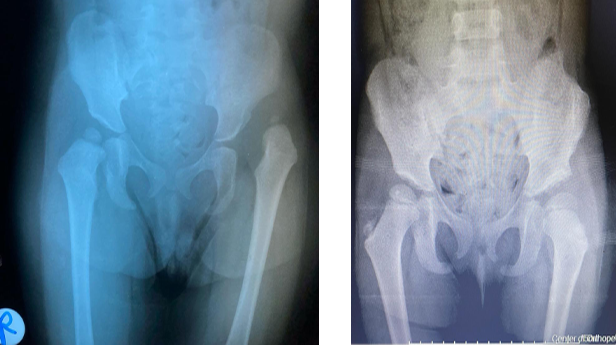

خلل التنسُّج الوركي ما بين الأطفال والمراهقين

يمكن لطبيب الأطفال اكتشاف مرض خلل التنسُّج الوركي، أو تشخيصه بتصوير الألتراساوند (تصوير فوق صوتي)، وذلك في حالة ولادة الطفل بالوضع المقعدي. ويتولى فريقنا علاج الأطفال المصابين بهذا الخلل بالوسائل غير الجراحية، إلى جانب الإجراءات الجراحية إذا لزم الأمر.